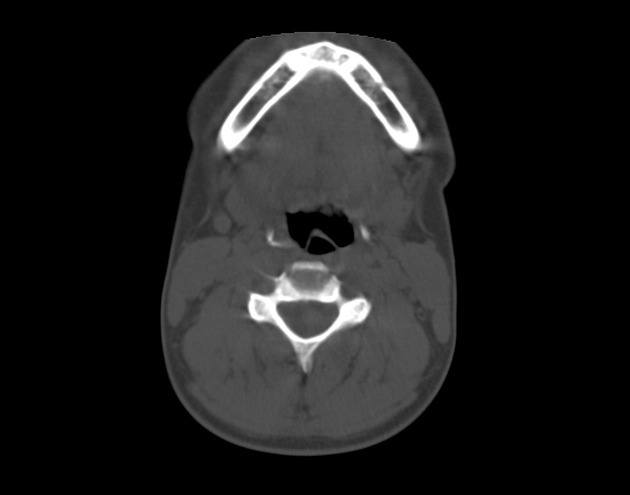

Gãy xương móng

» Thông tin: Nữ giới – 17 tuổi.

» Lâm sàng: Chấn thương vùng cổ.